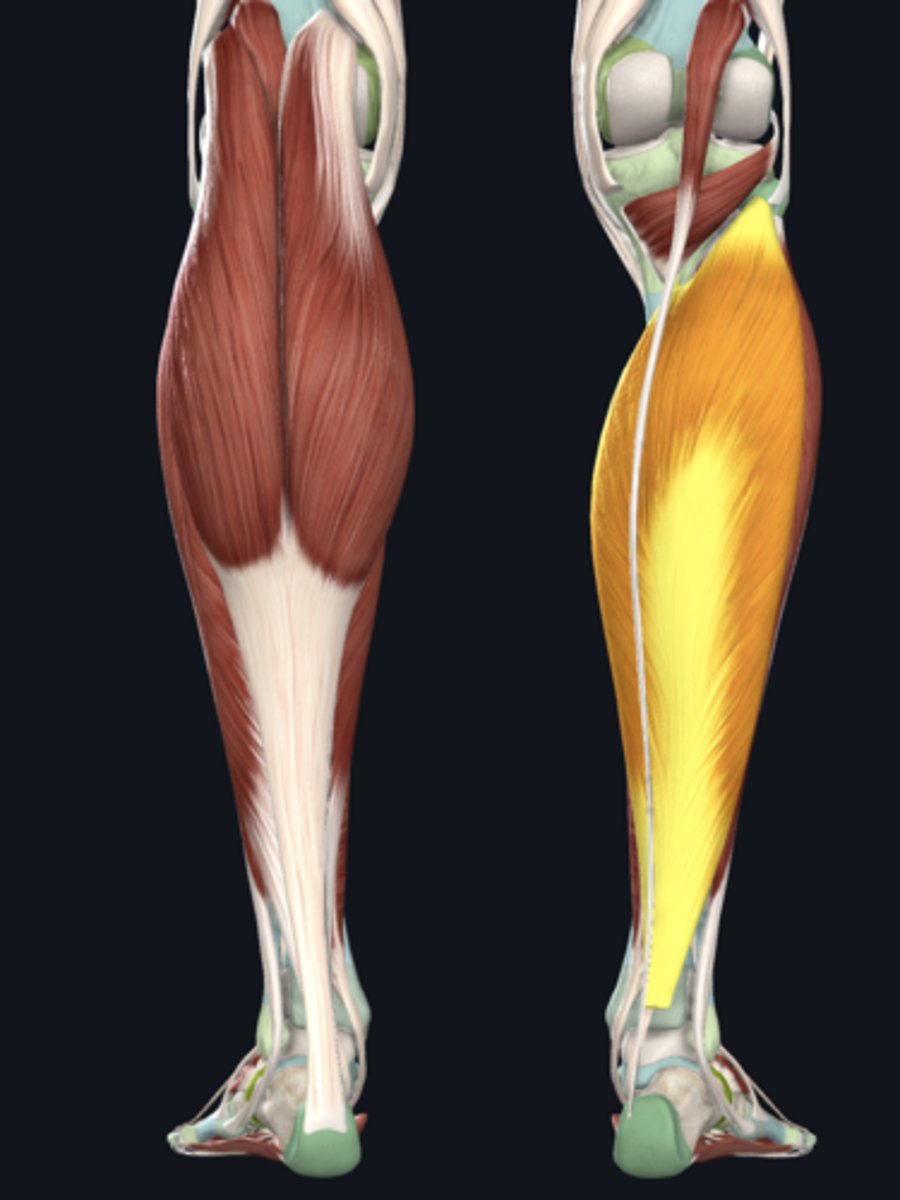

Medial head of gastrocnemius

Lateral head of gastrocnemius

Soleus

Plantaris